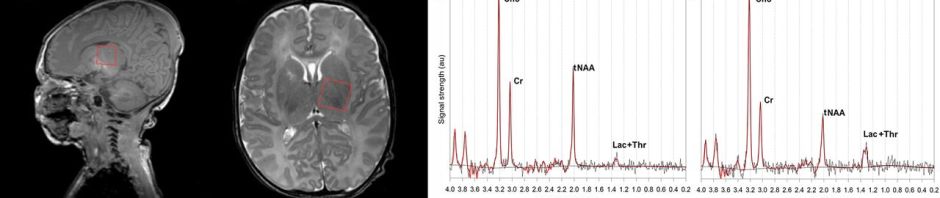

This figure shows basically what we are discussing, placing the voxel of interest in the thalamus, and then looking at the proton spectrum.

According to the framework for practice, the lactate to NAA ratio is highly predictive of adverse outcomes. Mitra et al (from where I took that image) refers to the Lac+Thr/tNAA (total NAA) which I think is the same thing as what Lally et al call the Lactate-NAA ratio. Barta et al also report that they calculated the Lac/NAA ratio, but that it was not one of the 3 ratios that adequately discriminated between the “good and poor outcome groups”.